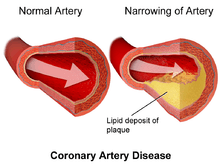

Chest pain that occurs regularly with activity, after eating, or at other predictable times is termed stable angina and is associated with narrowings of the arteries of the heart.

Typically, coronary artery disease occurs when part of the smooth, elastic lining inside a coronary artery (the arteries that supply blood to the heart muscle) develops atherosclerosis. With atherosclerosis, the artery's lining becomes hardened, stiffened, and swollen with calcium deposits, fatty deposits, and abnormal inflammatory cells - to form a plaque. Deposits of calcium phosphates (hydroxyapatites) in the muscular layer of the blood vessels appear to play not only a significant role in stiffening arteries but also for the induction of an early phase of coronary arteriosclerosis. This can be seen in a so-called metastatic mechanism of calciphylaxis as it occurs in chronic kidney disease and haemodialysis (Rainer Liedtke 2008). Although these patients suffer from a kidney dysfunction, almost fifty percent of them die due to coronary artery disease. Plaques can be thought of as large "pimples" that protrude into the channel of an artery, causing a partial obstruction to blood flow. Patients with coronary artery disease might have just one or two plaques, or might have dozens distributed throughout their coronary arteries. A more severe form is chronic total occlusion (CTO) when a coronary artery is completely obstructed for more than 3 months.[46]